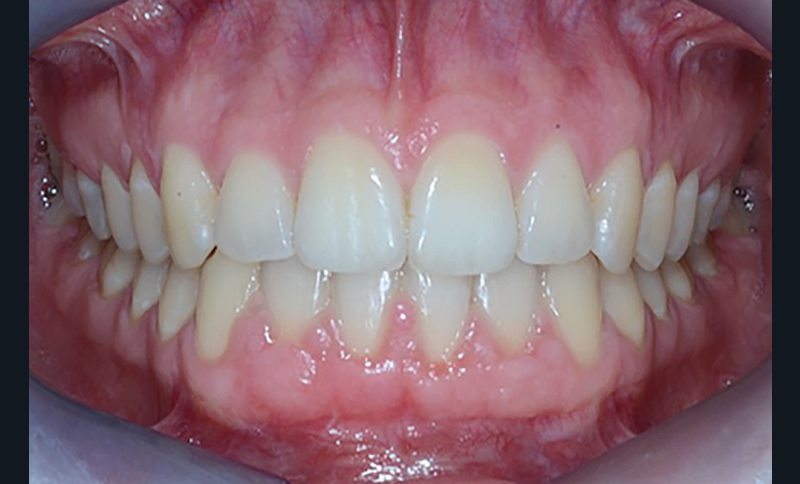

C’est à ces questions que nous permettront de répondre les deux premiers conférenciers, parodontologistes : le Dr Béatrice Straub nous présentera le renfort parodontal minéralisé, technique qu’elle a développée et pratique depuis de nombreuses années, pour éviter les préjudices des mouvements orthodontiques à risque, notamment lors des décompensations préchirurgicales (fig. 1a-d) ; le Pr Anton Sculean abordera le thème des greffes, avec leurs indications, les différentes techniques à privilégier et illustrera ses propos par de nombreux cas cliniques aux résultats esthétiques impressionnants.